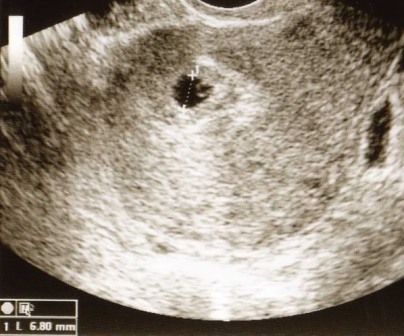

4.0 vagyok most. Be akartam reggel adatni a H1N1 elleni oltást, de nem tudtam, hogy sikerült-e a bébi (de gyanakodtam, mert tegnap vacsoráztam, majd rohantam hányni, ami eddig nem volt egyik terhességnél sem jellemző, úgyhogy megfogant a gyanú - is), ezért csináltam egy tesztet. Mesinek pont ma kellett volna jönnie, mindig napra pontos, ami egy áldás, szóval nagyon halovány csík lett 25-ös teszttel, nem reggeli anyagból. Csináltam egy másik félét később, az ugyanaz a halvány csík. Már hamarabb akartam oltást, de mindig valami ovisvírus rajta volt a családon, így nem adták be. Most ezen körülmények között nagyon vártam, hogy megjöjjön és tavasszal folytattuk volna a projektet. Kis Lelkem nem így gondolta

Én még csak Elevitet szedek, meg C-vitamint. Magnéziumot majd később. Csináltam vonalzót, talán nem korai, mindenesetre januárban megyek nőgyógyhoz uh-ra, ünnepek között kétlem, hogy rendel, bár... majd megérdeklődöm. REmélem, holnapra erősebb lesz a tesztem, minden órával egyre jobban beleélem magam most, hogy így sietett a bébi.